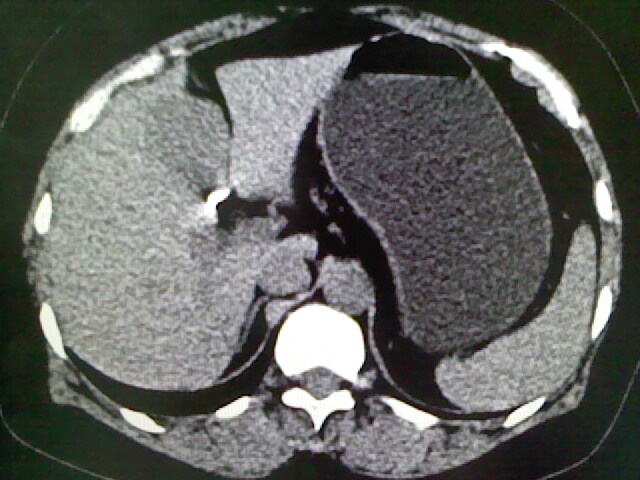

以下是引用卜一在2009-4-2 13:26:00的发言:[br]胆囊颈部结石伴胆囊炎!另:建议增强,待除外肝内占位及胆囊占位!

以下是引用liaoqiang在2009-4-2 16:23:00的发言:[br]胆囊是否切除?胆囊颈区致密影考虑金属夹?结石?肝脏右叶低密度影,考虑增强。